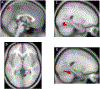

The gut microbiota has recently gained attention as a possible modulator of brain activity. A number of reports suggest that the microbiota may be associated with neuropsychiatric conditions such as major depressive disorder, autism and anxiety. The gut microbiota is thought to influence the brain via vagus nerve signalling, among other possible mechanisms. The insula processes and integrates these vagal signals. To determine if microbiota diversity and structure modulate brain activity, we collected faecal samples and examined insular function using resting state functional connectivity (RSFC). Thirty healthy participants (non-smokers, tobacco smokers and electronic cigarette users, n = 10 each) were studied. We found that the RSFC between the insula and several regions (frontal pole left, lateral occipital cortex right, lingual gyrus right and cerebellum 4, 5 and vermis 9) were associated with bacterial microbiota diversity and structure. In addition, two specific bacteria genera, Prevotella and Bacteroides, were specifically different in tobacco smokers and also associated with insular connectivity. In conclusion, we show that insular connectivity is associated with microbiome diversity, structure and at least two specific bateria genera. Furthemore, this association is potentially modulated by tobacco smoking, although the sample sizes for the different smoking groups were small and this result needs validation in a larger cohort. While replication is necessary, the microbiota is a readily accessible therapeutic target for modulating insular connectivity, which has previously been shown to be abnormal in anxiety and tobacco use disorders.